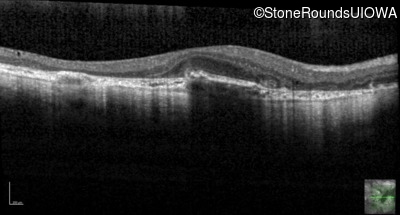

Age at visit: 51 years

This 51 year old woman first experienced some abnormality in her distance vision when she was 27 years old. She feels that her vision has been stable since that time.

Diagnosis & molecular findings

AR Stargardt Disease ABCA4 Gly1507Arg GGG>AGG IVS42+1 G>A AR